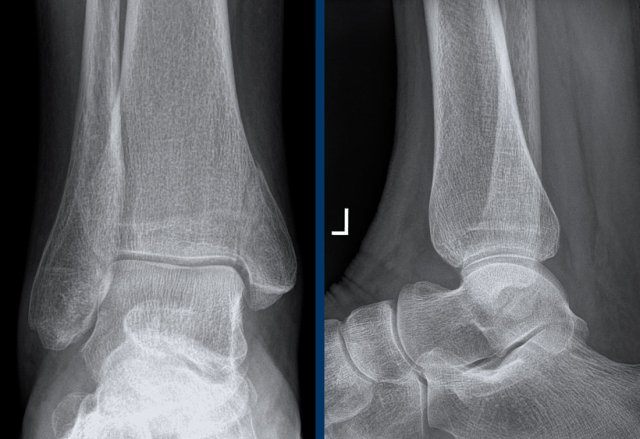

case 3 - ankle distortion

What are the findings?

What is the stage of this injury?

Click on the image for larger view.

Go to the discussion...